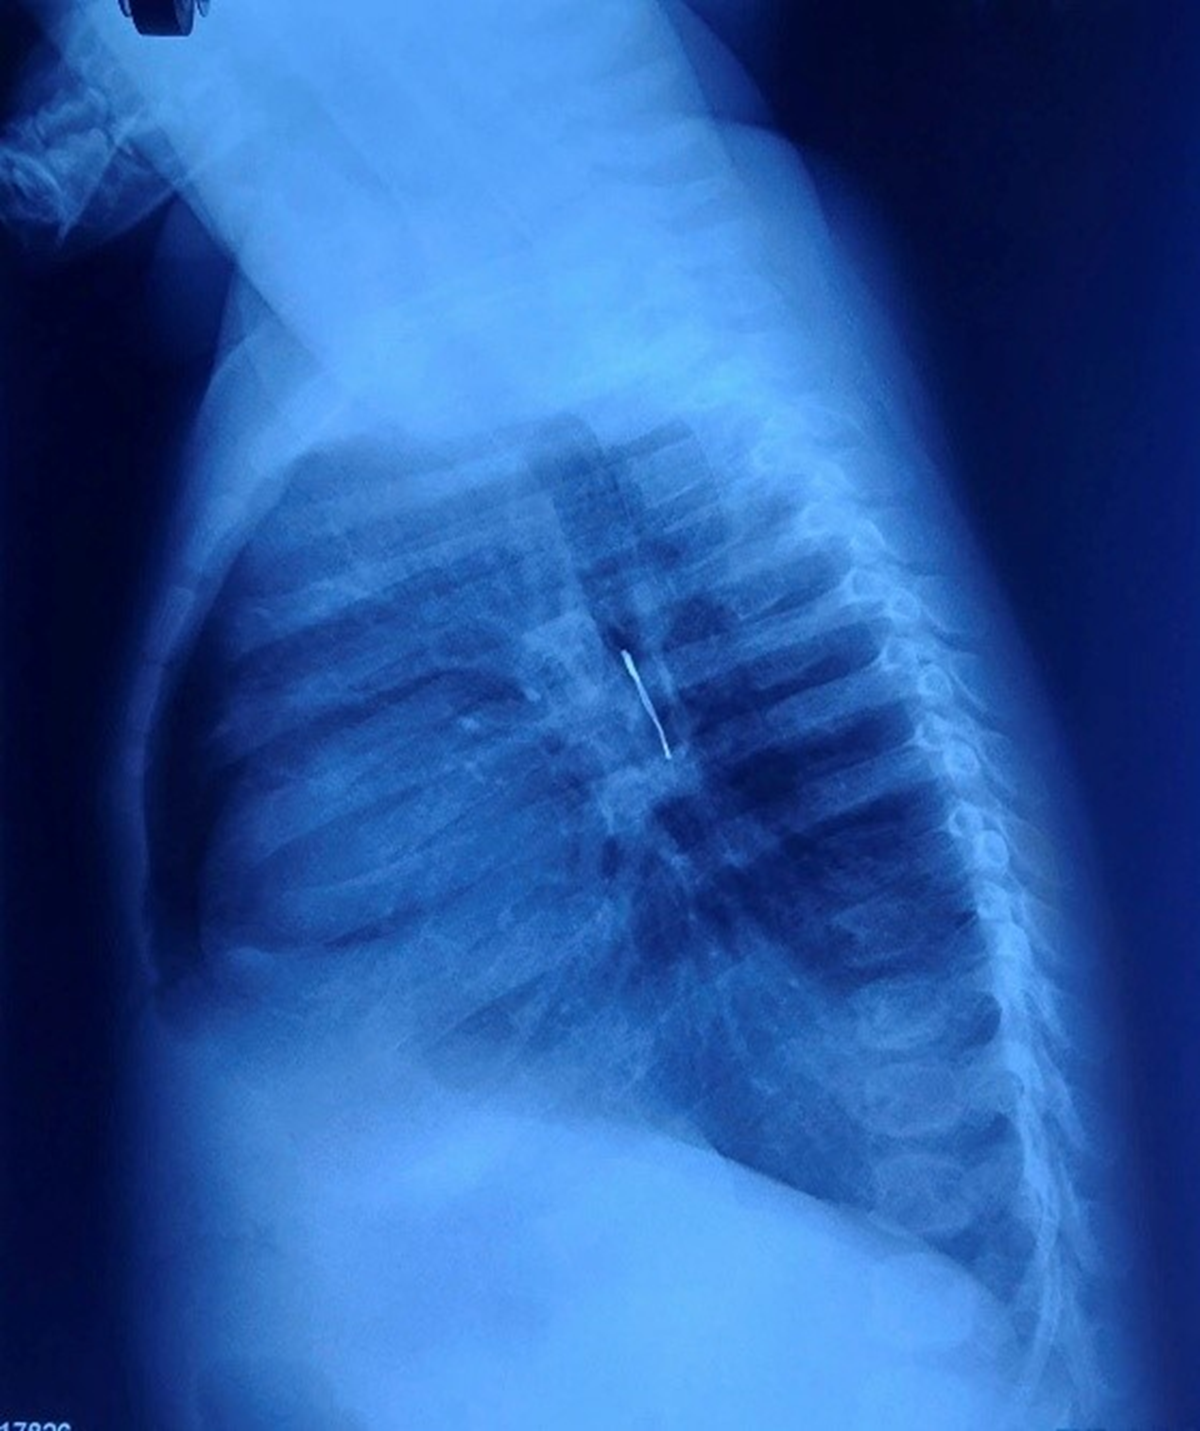

Hình ảnh X-quang: dị vật cản quang ở phế quản gốc phải, xẹp phổi phải không hoàn toàn và tràn khí trung thất.

Tại bệnh viện, kết quả chẩn đoán cho thấy dị vật cản quang nằm ở phế quản gốc phải, kèm theo tình trạng xẹp phổi phải không hoàn toàn và tràn khí trung thất.